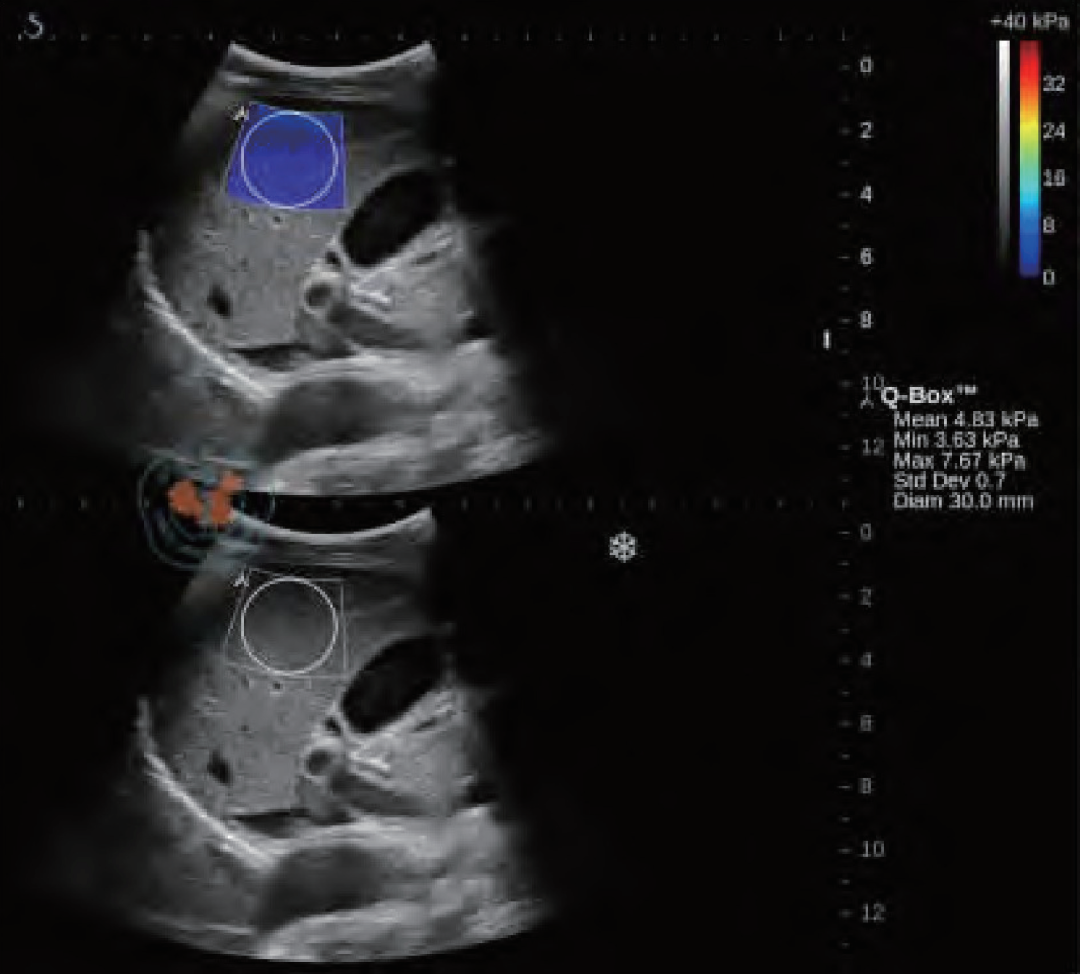

图12 慢性肝病患者的肝脏剪切波弹性成像及定量分析图。下图是原始的成像图,上图的蓝色区域则是在成像区域内选取直径为3 mm的圆形定量检测区域进行弹性模量的检测

谐波运动成像最早由Maleke等人提出。通过探头产生的超声波对组织施加周期性的声辐射力,使组织产生谐波运动。 通过获取组织被激发前后的B超图像并对其进行运动估计,可以间接反映组织的弹性状况。该方法可以准确反映深部组织的局部弹性状况,但由于需要在激发信号的同时监测组织的运动,因而采集到的B超信号容易受到激发信号的严重干扰,这是该成像方法迄今为止尚未得到完美解决的主要问题。当声辐射力作用在组织上时会激发出剪切波,剪切波弹性成像正是通过检测这一剪切波的传播来达到成像的目的,最早由美国学者Sarvazyan和Emelianov提出。他们利用高强度聚焦超声探头产生声辐射力,在人体组织中产生了明显的剪切波,并运用磁共振成像方法监测该剪切波的传播情况。由于剪切波速与人体组织的粘弹特性紧密相关,因此通过检测剪切波的传播速度等参数可以获取组织的弹性信息。图12显示了某一慢性肝病患者的肝脏弹性成像图。声辐射力脉冲成像技术最早由杜克大学的学者Nightingale等人提出,该方法通过高能聚焦超声探头在局部组织中产生短暂的高强度声辐射力,从而推动组织产生一定的应变,再通过追踪这些微小应变和剪切波的传播来判断组织的粘弹特性。研究人员发现,组织对于脉冲声辐射力的瞬态响应直接相关于局部区域的硬度大小,而通过求解亥姆霍兹方程的反问题方法可以量化组织中剪切波的波速。Nightingale等通过详细的数值仿真和体模研究证实了声辐射力脉冲成像的可行性,并得到了与传统B超图像相比更高的对比度和分辨力。如今的声辐射力脉冲成像已在临床上具备多种脏器检查的能力,图13显示了某位良性纤维瘤患者的乳腺声辐射力脉冲成像图。